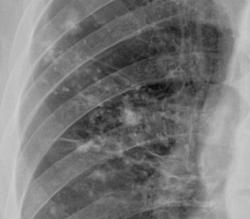

Правостороняя очаговая пневмония.

Очаговая (сливная) пневмония в 6 сегменте.

Крупноочаговые тени - метастазы справа медио-базально. Фрагменты томограмм.